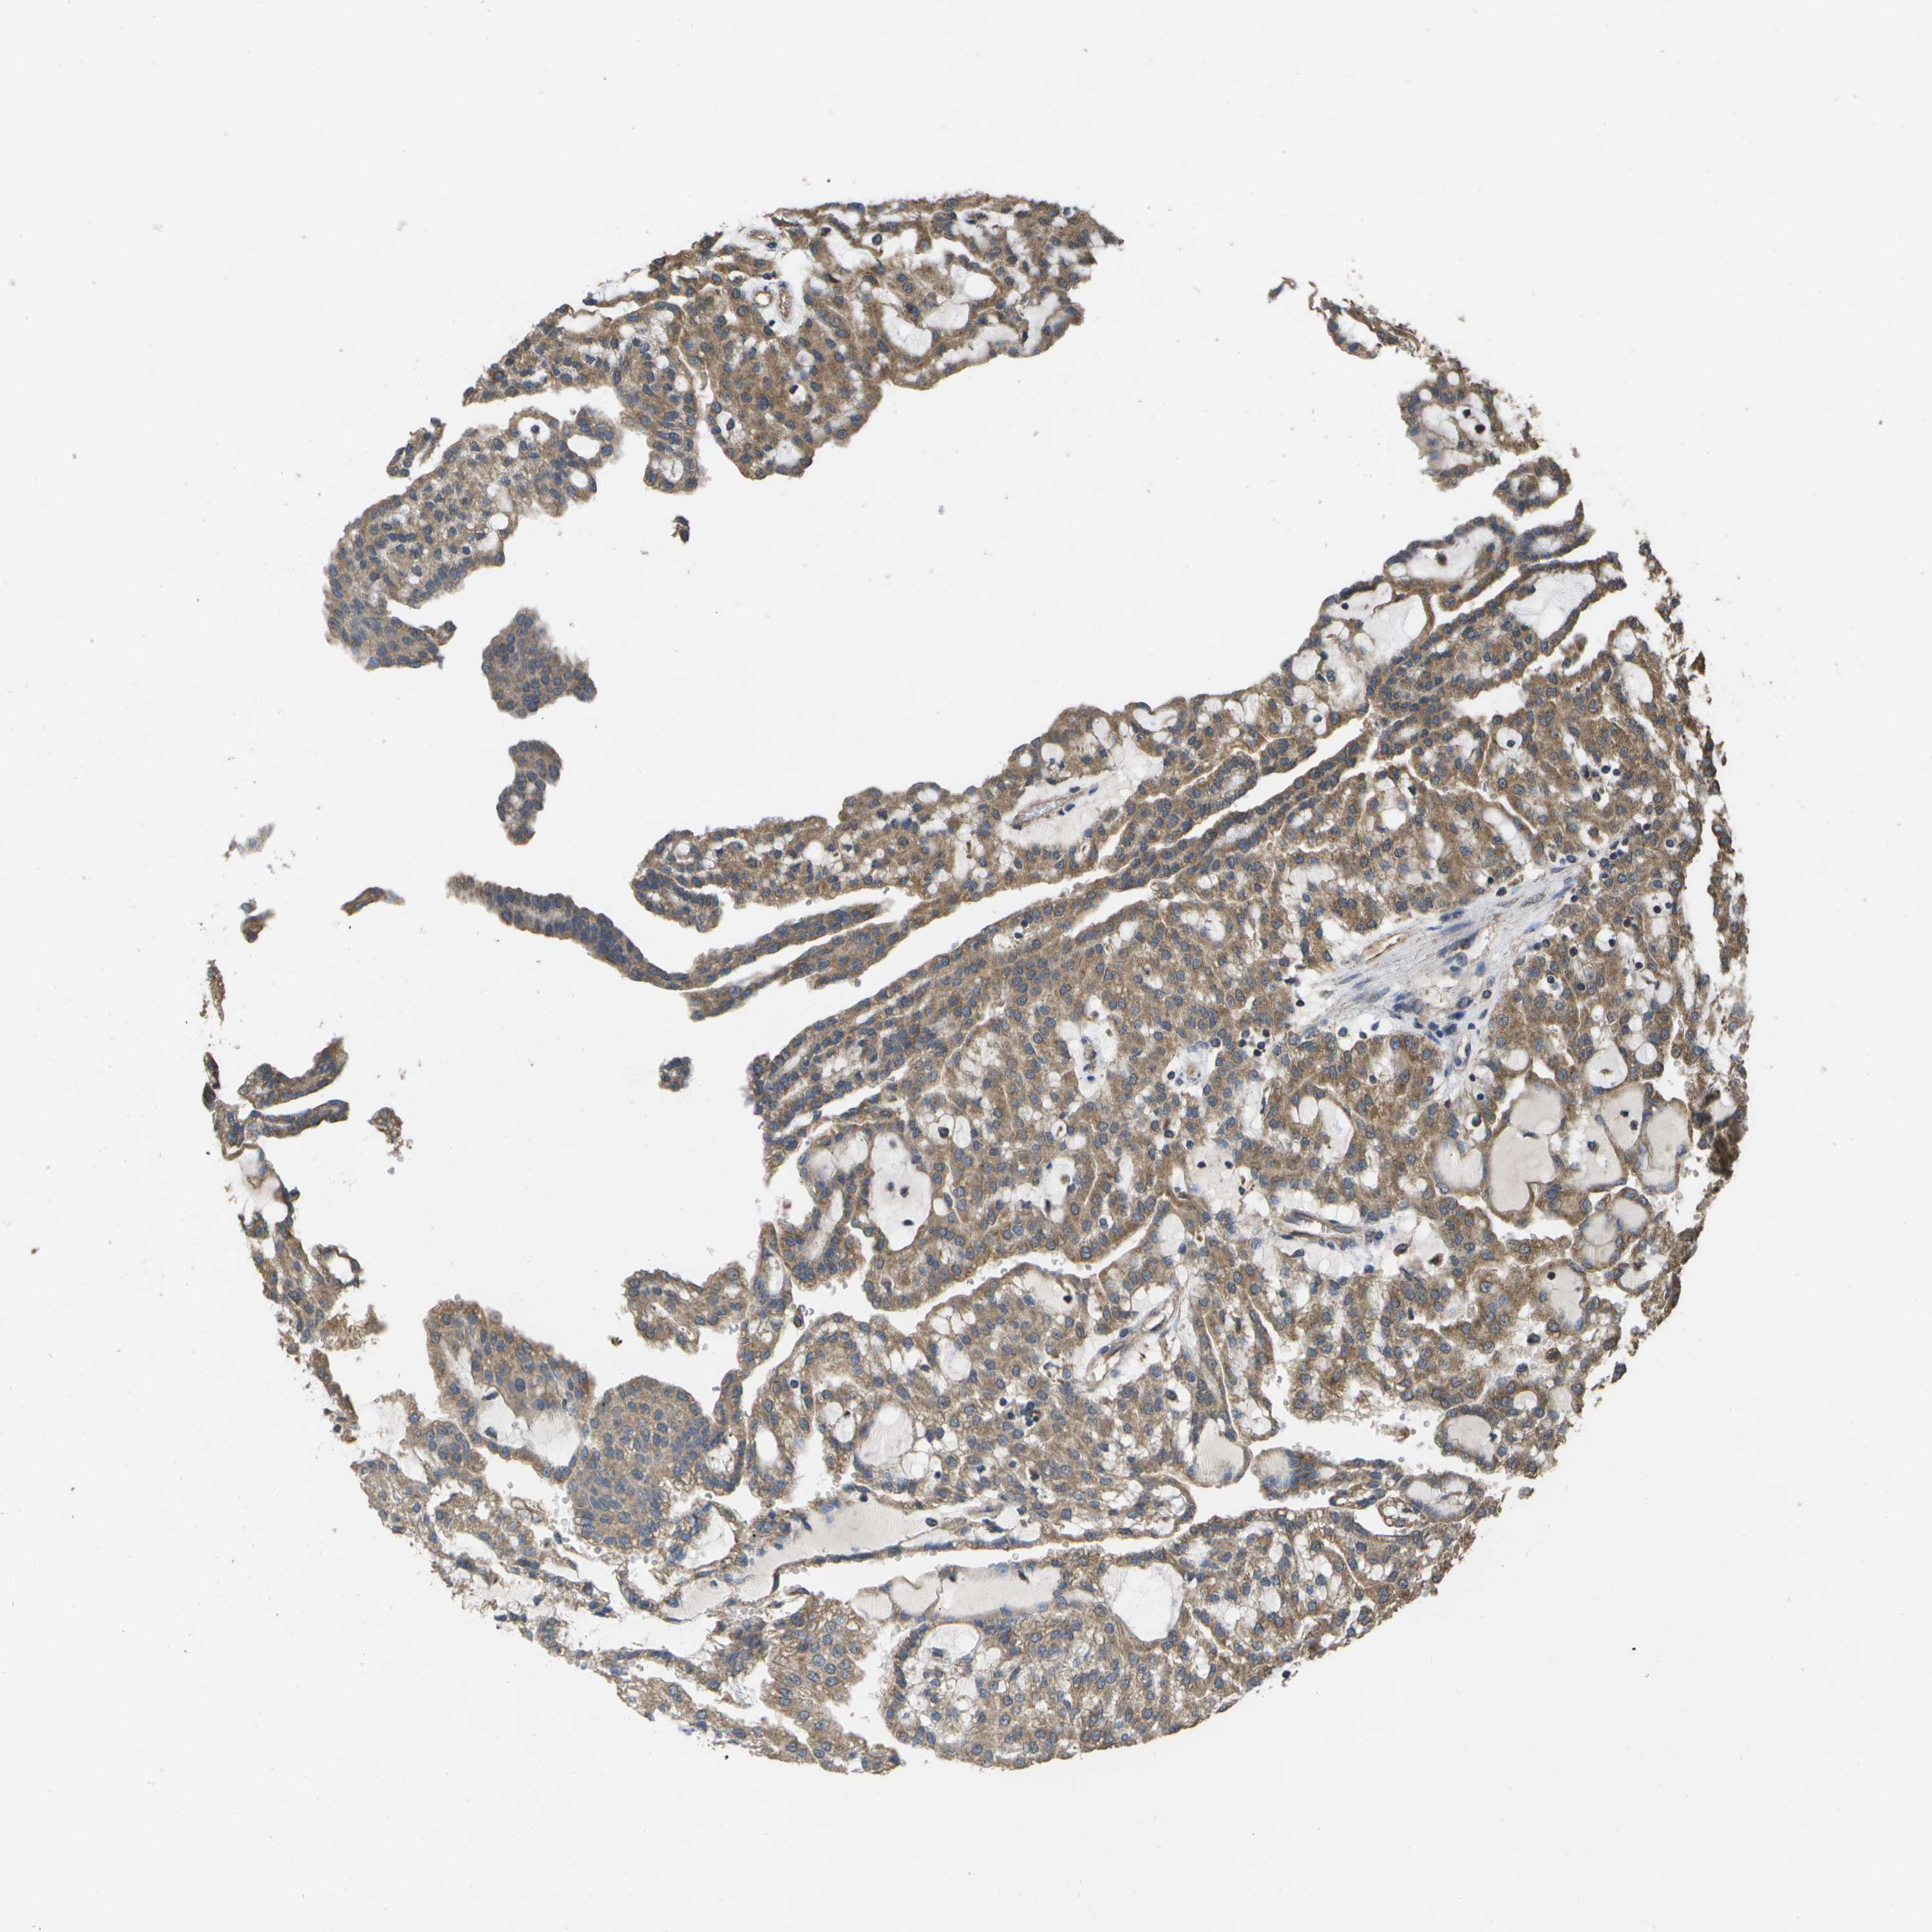

KIDNEY RENAL CLEAR CELL CARCINOMA (VALIDATION) - Interactive survival scatter ploti

The Survival Scatter plot shows the clinical status (i.e. dead or alive) for all individuals in the patient cohort, based on the same data that underlies the corresponding Kaplan-Meier plots. Patients that are alive at last time for follow-up are shown in blue and patients who have died during the study are shown in red.

The x-axis shows the expression levels (FPKM) of the investigated gene in the tumor tissue at the time of diagnosis. The y-axis shows the follow-up time after diagnosis (years). Both axes are complimented with kernel density curves demonstrating the data density over the axes. The top density plot shows the expression levels (FPKM) distribution among dead (red) and alive patients (blue). The right density plot shows the data density of the survived years of dead patients with high and low expression levels respectively, stratified using the cutoff indicated by the vertical dashed line through the Survival Scatter plot. This cutoff is automatically defined based on the FPKM cutoff that minimizes the p-score. The cutoff can be changed by dragging the vertical line or by entering a cutoff value in the square labeled "Current cut-off".

Under the Survival Scatter plot the p-score landscape (black curve; left axis) is shown together with dead median separation (red curve; right axis). Dead median separation is the difference in median mRNA expression between patients who have died with high and low expression, respectively. It is calculated as follows: median FPKM expression of dead patients with high expression - median FPKM expression of dead patients with low expression. This is intended to aid the user in visually exploring custom cutoffs and the associated p-scores and dead median separation.

Individual patient data is displayed and can be filtered by clicking on one or more of the category buttons on the top of the page. Categories describing expression level and patient information include: high, low, alive, dead, female, male and tumor stages. The scale of the x-axis can be toggled between linear and log-scale by clicking on the "x log" button. Mouse-over function shows TCGA ID, patient information and mRNA expression (FPKM) for each patient.

& Survival analysisi

Kaplan-Meier plots summarize results from analysis of correlation between mRNA expression level and patient survival. Patients were divided based on level of expression into one of the two groups "low" (under cut off) or "high" (over cut off). X-axis shows time for survival (years) and y-axis shows the probability of survival, where 1.0 corresponds to 100 percent.

SACS is not prognostic in Kidney Renal Clear Cell Carcinoma (validation)

Best expression cut offi

Based on the FPKM value of each gene, patients were classified into two groups and association between prognosis (survival) and gene expression (FPKM) was examined. The best expression cut-off refers the FPKM value that yields maximal difference with regard to survival between the two groups at the lowest log-rank P-value. Best expression cut-off was selected based on survival analysis .

When clicking on this number, the vertical dashed line indicating cut-off, the interactive survival plot, and the Kaplan-Meier curve will be adjusted to show results based on the best expression cut-off.

: 3.62

TCGA RNA samplesi

RNA-seq data is reported as average FPKM (number Fragments Per Kilobase of exon per Million reads), generated by the The Cancer Genome Atlas (TCGA) .

Normal distribution across the dataset is visualized with box plots, shown as median and 25th and 75th percentiles. Points are displayed as outliers if they are above or below 1.5 times the interquartile range. FPKM values of the individual samples are presented next to the box plot.

Average pTPM 4.3

Number of samples 100